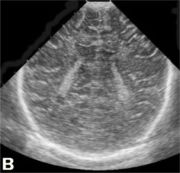

| Перивентрикулярный отек а, б, в, г - ребенок 2-х суток жизни с вдавленным переломом левой теменной кости. Структуры головного мозга симметричны. Сканирование во фронтальной и саггитальной плоскостях выявляет повышение эхогенности в перивентрикулярных областях без эхо-признаков других патологических изменений. При ДГ - невыраженное повышение показателей периферического сопротивления (спазм сосудов) д, е, ж - ребенок 1-х суток жизни от травматичных родов, парез Эрба слева, петехиальные кровоизлияния на лице, кровоизлияния в склеры, оценка по Apgar - 3-5 баллов. Определяется значительное повышение эхогенности в перивентрикулярной области, при ДГ - снижение показателей периферического сопротивления (парез сосудов). Перивентрикулярная лейкомаляция

|  |  | | а, б, в - фронтальные. |  |  | г, д - саггитальные сканы в разных плоскостях, В-режим. Определяются зоны перивентрикулярной лейкомаляции с обеих сторон. | Перивентрикулярное кровоизлияние в стадии псевдокисты